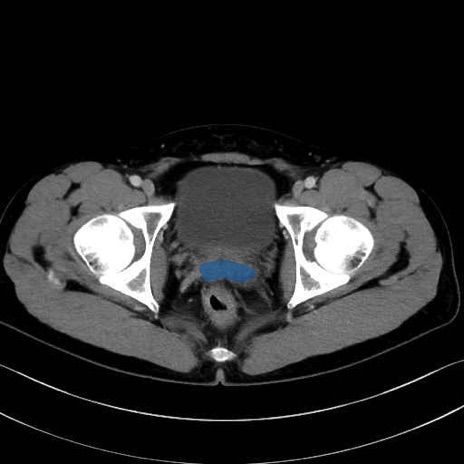

精嚢(seminal vesicle)のCT画像における解剖

症例

【症例】20歳代 男性 スクリーニング